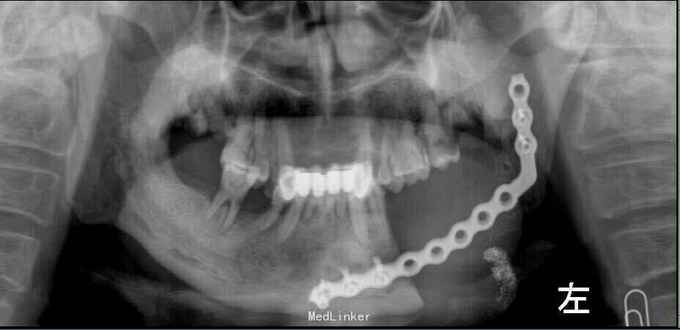

诊断:左下牙龈鳞癌伴左下颌骨、左颈淋巴转移 治疗:入院后行术前常规辅查,T99全身核素扫描结果示左下颌骨放射状性分布浓缩影,结合病史考虑肿瘤左下颌骨转移。于2012年11月20日开始用平阳霉素行术前诱导化疗;并行颈部CT增强扫描考虑有颈部淋巴结转移。12月8日化疗结束平阳总剂量达160mg;肿瘤体积缩小约30%。复查血生化、血气、胸片未见肺纤维化。为尽量达到预期治疗的目的,医生术前与患者及家属进行充分沟通,征得同意后于12月18日在全麻下为患者行'左侧改良性颈淋巴清扫术十左下牙龈癌切除术十左下颌骨阶段切除术十左下颌骨重建钛板连接朮十左胸大肌带肋骨岛状肌皮瓣转移修复术。手术历经约8h,输血800ml,术中并送切缘冰冻报告为阴性,术后于ICU复苏拔管,次日回病房行留置胃管、防感染等综合治疗。